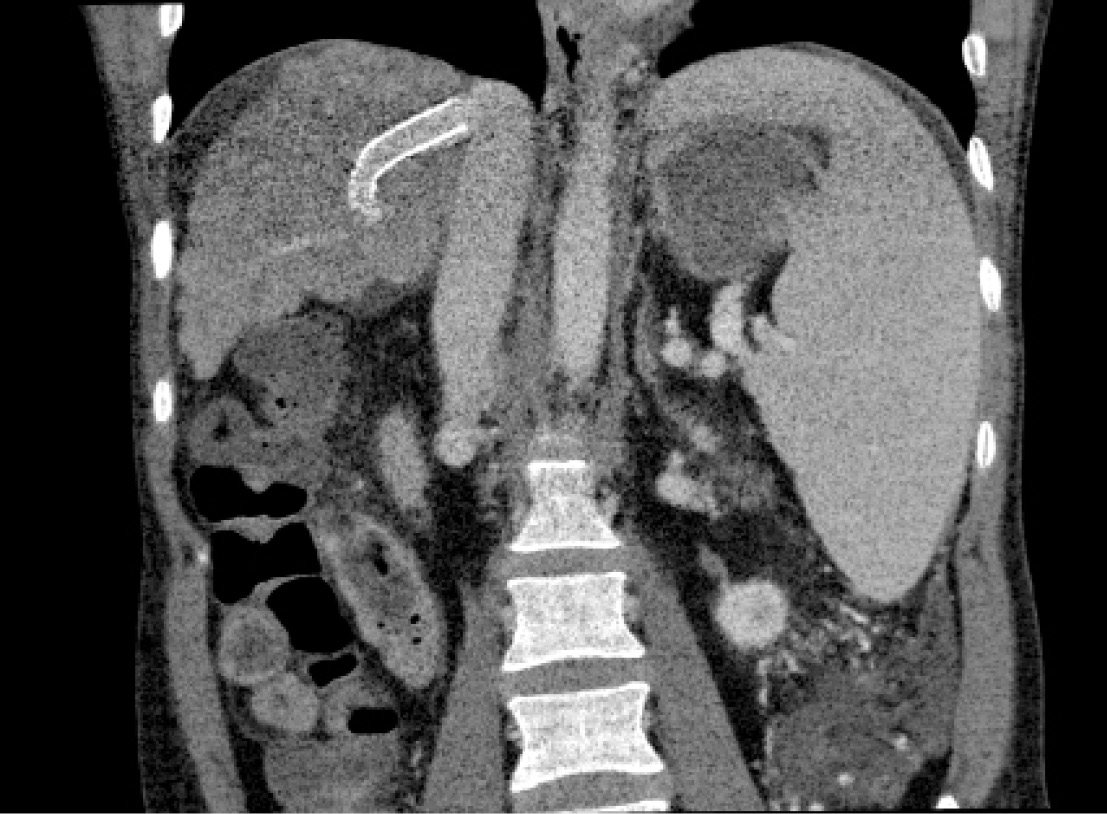

Рис. 1. Контрольная портография после выполнения TIPS

В клиниках общей хирургии и госпитальной хирургии ВМедА больной выполнены 2 операции криосорбции, ультрафильтрации и реинфузии асцитической жидкости, 2 сеанса эндоскопического лигирования вен пищевода. С целью коррекции тромбоцитопении пациентке 12.02.2008 г. произведена эмболизация селезеночной артерии с положительным эффектом. Уровень тромбоцитов в периферической крови повысился с 25–40 × 109/л до 75–100 × 109/л. Однако асцитический синдром у больной не купировался. Решением консилиума традиционные шунтирующие операции у пациентки признаны невозможными в связи с декомпенсацией цирроза печени и наличием гигантской опухоли брюшной полости и малого таза (более 20 см в диаметре). В то же время оперативное лечение по поводу опухоли было связано с высоким риском в связи с наличием диуретикорезистентного асцита, выраженного варикозного расширения вен пищевода, печеночной недостаточности. Кроме того, больной было отказано в постановке на лист ожидания трансплантации печени из-за наличия опухоли. Учитывая рецидивирующее течение диуретикорезистентного асцита, высокий риск рецидива пищеводных кровотечений, пациентке 05.03.2008 г. выполнено трансъюгулярное интрапеченочное портосистемное шунтирование (TIPS) под местной анестезией (рис. 1).

Особенностью оперативного вмешательства было проведение транспеченочной пункции воротной вены при смещенной печени (за счет опухоли больших размеров). Кроме того, у пациентки отмечены выраженная деформация и смещение верхней брыжеечной вены, ствола воротной вены. После установки стента произошло снижение портального давления с 550 до 280 мм вод. ст. Послеоперационный период протекал без осложнений. У пациентки отмечено купирование диуретикорезистентного асцита. Варикозное расширение вен пищевода снизилось до 1–2 ст.

Пациентка наблюдается в течение 12 лет. При регулярных контрольных обследованиях признаков рецидива онкологического заболевания не выявлено. В 2017 г. пациентка прошла полный курс безинтерфероновой терапии противовирусными препаратами прямого действия по поводу хронического вирусного гепатита С. На фоне элиминации вируса отмечена положительная динамика в функциональных показателях печени. У пациентки на настоящий момент печеночная недостаточность класса А (Child-Pugh). При выполнении контрольной КТ-ангиографии TIPS проходим (рис. 4 А, Б). Асцита нет. Варикозное расширение вен пищевода 1-й ст. Прогрессирования печеночной энцефалопатии не отмечено. Пациентка профилактически получает препараты лактулозы и орнитина.